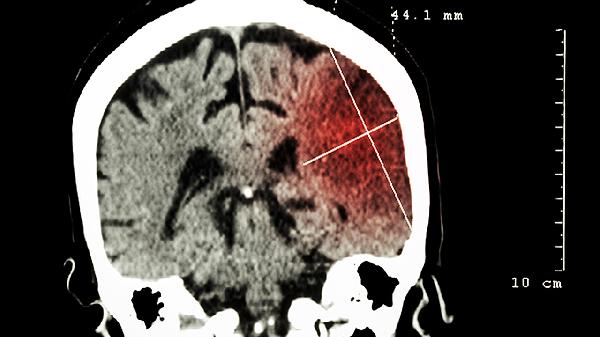

5、辅助治疗脑部疾病

在医生指导下,益智康脑丸可作为某些脑部疾病的辅助治疗药物。对于轻度认知障碍、脑血管疾病后遗症等病症,该药物可能帮助改善部分症状。但需明确,它不能替代主要治疗药物,患者应严格遵循医生的综合治疗方案,定期复查评估疗效。